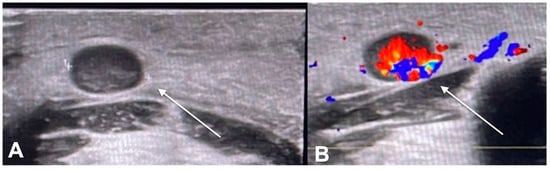

- Catalano, O.; Roldán, F.A.; Varelli, C.; Bard, R.; Corvino, A.; Wortsman, X. Skin cancer: Findings and role of high-resolution ultrasound. J. Ultrasound 2019, 22, 423–431. [Google Scholar] [CrossRef] [PubMed]

- Wang, S.-Q.; Liu, J.; Zhu, Q.-L.; Zhao, C.-Y.; Qu, T.; Li, F.; Wortsman, X.; Jin, H.-Z. High-frequency ultrasound features of basal cell carcinoma and its association with histological recurrence risk. Chin. Med. J. 2019, 132, 2021–2026. [Google Scholar] [CrossRef]

- Reginelli, A.; Belfiore, M.P.; Russo, A.; Turriziani, F.; Moscarella, E.; Troiani, T.; Brancaccio, G.; Ronchi, A.; Giunta, E.F.; Sica, A.; et al. A Preliminary Study for Quantitative Assessment with HFUS (High- Frequency Ultrasound) of Nodular Skin Melanoma Breslow Thickness in Adults Before Surgery: Interdisciplinary Team Experience. Curr. Radiopharm. 2020, 13, 48–55. [Google Scholar] [CrossRef]

- Belfiore, M.P.; Reginelli, A.; Russo, A.; Russo, G.M.; Rocco, M.P.; Moscarella, E.; Ferrante, M.; Sica, A.; Grassi, R.; Cappabianca, S. Usefulness of High-Frequency Ultrasonography in the Diagnosis of Melanoma: Mini Review. Front. Oncol. 2021, 11, 673026. [Google Scholar] [CrossRef]